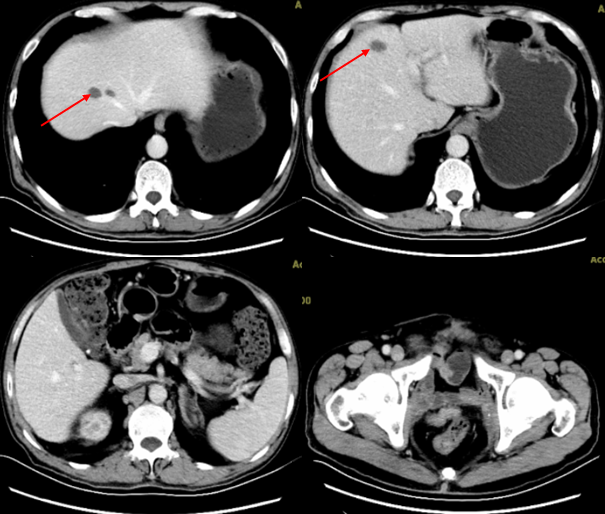

2019-3-29复查全腹部CT增强示:肝脏及盆腔内多发转移瘤;对比2019.3.1前片,肝脏及盆腔转移瘤均明显缩小(图5)。后规律复查CT,表现基本相仿。

图5 患者肝脏及盆腔转移瘤继续缩小,疗效评估为部分缓解(PR;2019年3月29日)

2019-6-18患者复查腹部增强CT:1.肝左叶病灶,转移?2.右输尿管上段病变,炎症?转移性病变?(图6)。2019-8-10复查腹部增强CT:1.肝左叶异常信号灶,请结合MRI增强?2.腹膜后多发小淋巴结,对比2019-6-18大致相仿(图7)。2019年8月16日上腹部MR增强:1.肝右叶S4段占位,倾向囊肿;2.肝左叶异常灌注考虑(图8)。

患者2019年1月25日(发现盆腔多发转移病灶后1个月)检查发现肝脏出现多发转移性肿瘤,考虑患者病情进展迅速且疾病负荷较大,而免疫治疗起效相对较晚,调整治疗方案为信迪利单抗免疫治疗联合白蛋白紫杉醇化疗。治疗期间定期复查,肝脏转移灶和盆腔病灶明显缩小及消失,疗效PR。截至2019年9月,患者共接受白蛋白紫杉醇(100mg)qw化疗23次,末次化疗时间2019年8月,信迪利单抗(200mg)q3w治疗13次,末次治疗时间2019年9月18日,一线治疗PFS为9个月。